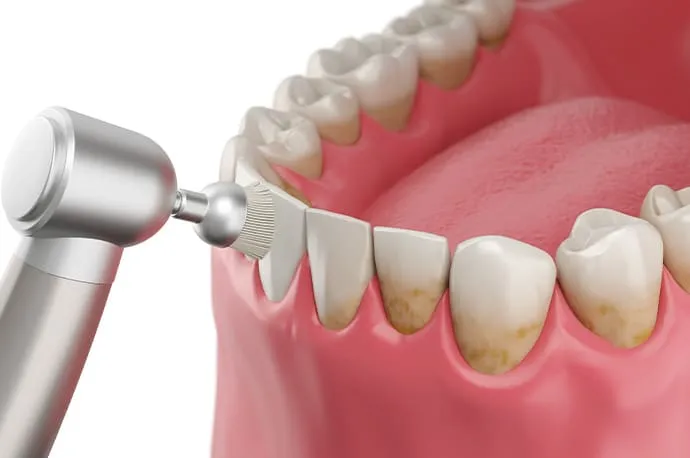

PMTC(プロフェッショナルケア)

回転ブラシなどを使い、歯の汚れや着色をしっかり落とします。